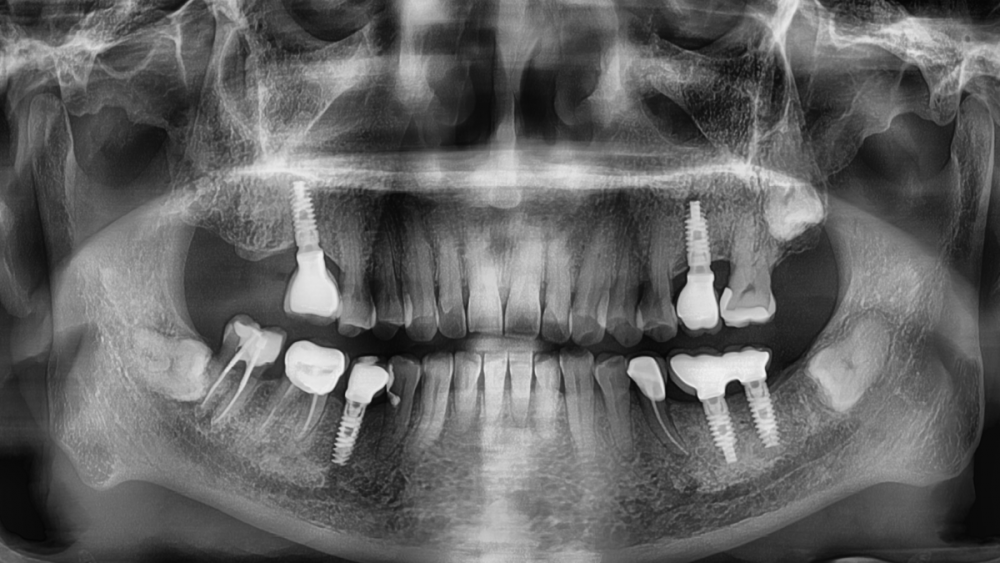

Irouil Опубликовано 8 августа, 2023 Автор Поделиться Опубликовано 8 августа, 2023 Ссылка на комментарий

АнтонТЛТ Опубликовано 8 августа, 2023 Поделиться Опубликовано 8 августа, 2023 Лучше прицельные снимки делать, на таких не рассмотреть ничего. Форум сильно сжимает изображение. Либо кадрировать эти снимки. Почему тибейсы такие короткие используются? Ссылка на комментарий

Irouil Опубликовано 9 августа, 2023 Автор Поделиться Опубликовано 9 августа, 2023 @АнтонТЛТ думаете короткие ти бейсы могут повлиять? Я сейчас не про пассивность. Лаба работает вообще с большим количеством нареканий, самое смешное в этом то, что она наша)) @NazranDantist согласен, есть риски, что какие-то сели внатяг. Ссылка на комментарий